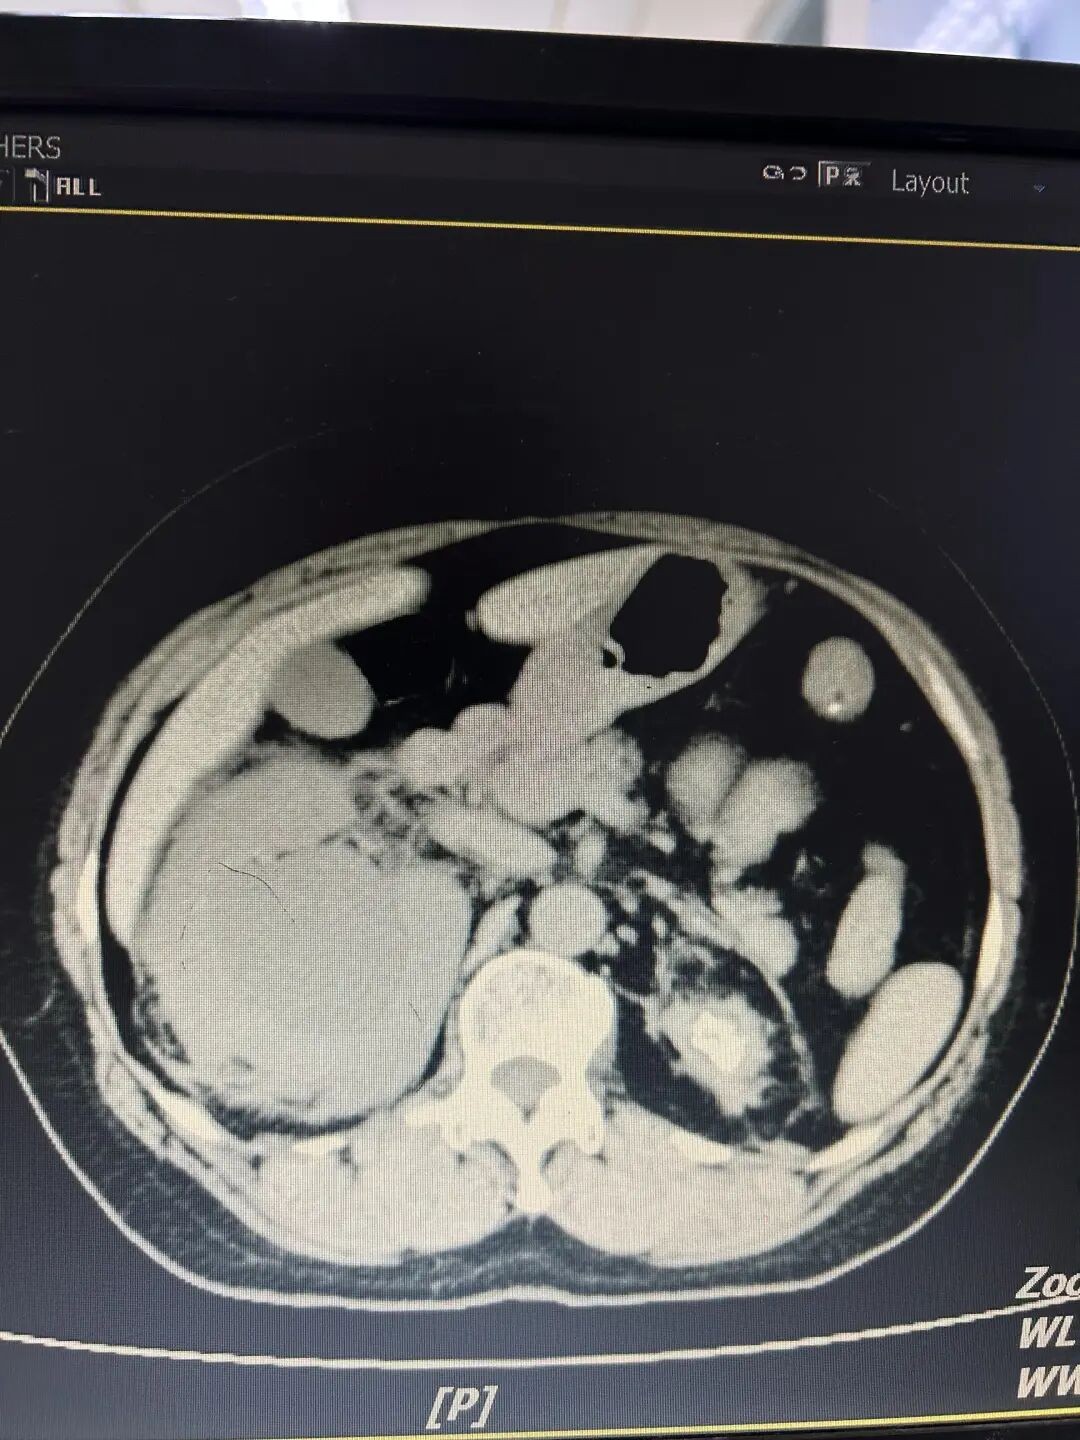

今年5月初,魏女士再次出现无明显诱因的右侧腰痛的症状,还伴有尿少、恶心、呕吐、乏力等症状,来到彭州市人民医院检查CT发现右肾积水问题已经非常严重,肾功能也出现异常,血肌酐升高,血常规也提示感染。

检查提示右肾重度积水肾周感染,左肾萎缩